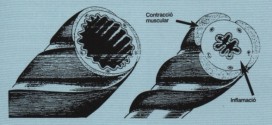

La arteritis obliterante. Dureza y engrosamiento anormales de las paredes arteriales, resultado de inflamaciones, especialmente de la túnica íntima con tendencia a la obliteración del vaso. Por: Salvador Gregori, binipatia.com Resumiendo: También llamada arteritis obliterante de los miembros inferiores (o AOMI), es una enfermedad que resulta de la disminución del calibre de las arterias que suministran sangre a las extremidades inferiores. …

La enfermedad pulmonar obstructiva crónica (EPOC) en ingles (COPD). El aire que usted respira baja por la tráquea a unas vías respiratorias llamadas bronquios, una especie de tubitos que se encuentran dentro de los pulmones. Dentro de los pulmones, los bronquios se ramifican en miles de tubos más pequeños y delgados llamados bronquíolos. Estos tubos terminan en racimos de sacos …

La palabra asma en la antigua Grecia significaba «jadear» y se utilizó como sinónimo de disnea hasta el XVII. Resumiendo: En épocas posteriores, a medida que fue aumentando el conocimiento sobre las enfermedades cardíacas y pulmonares, su significado se precisó y en la actualidad se utiliza sólo para designar una de las enfermedades respiratorias caracterizadas por obstrucción de la vía …

La inflamación pulmonar crónica. El pulmón es un órgano respiratorio que transporta el oxígeno respirado a través de la boca o nariz hacia el flujo sanguíneo. Los pulmones son uno de los órganos más importantes de nuestro cuerpo. Ellos ayudan en el proceso de la respiración y juegan un papel muy importante en el suministro de oxígeno al cuerpo. Los …

La hiperinflamacion torácica crónica. Es una enfermedad bronquio-pulmonar, que se le considera permanente (crónica), a saber. Es muy conveniente usar la Trofología, para conseguir la máxima garantía posible la mayor eficacia, en los tratamientos. Es una enfermedad inflamatoria crónica e intermitente de la vía aérea caracterizada por la obstrucción generalmente reversible a flujo aéreo, aunque puede ser severa e incluso mortal. …